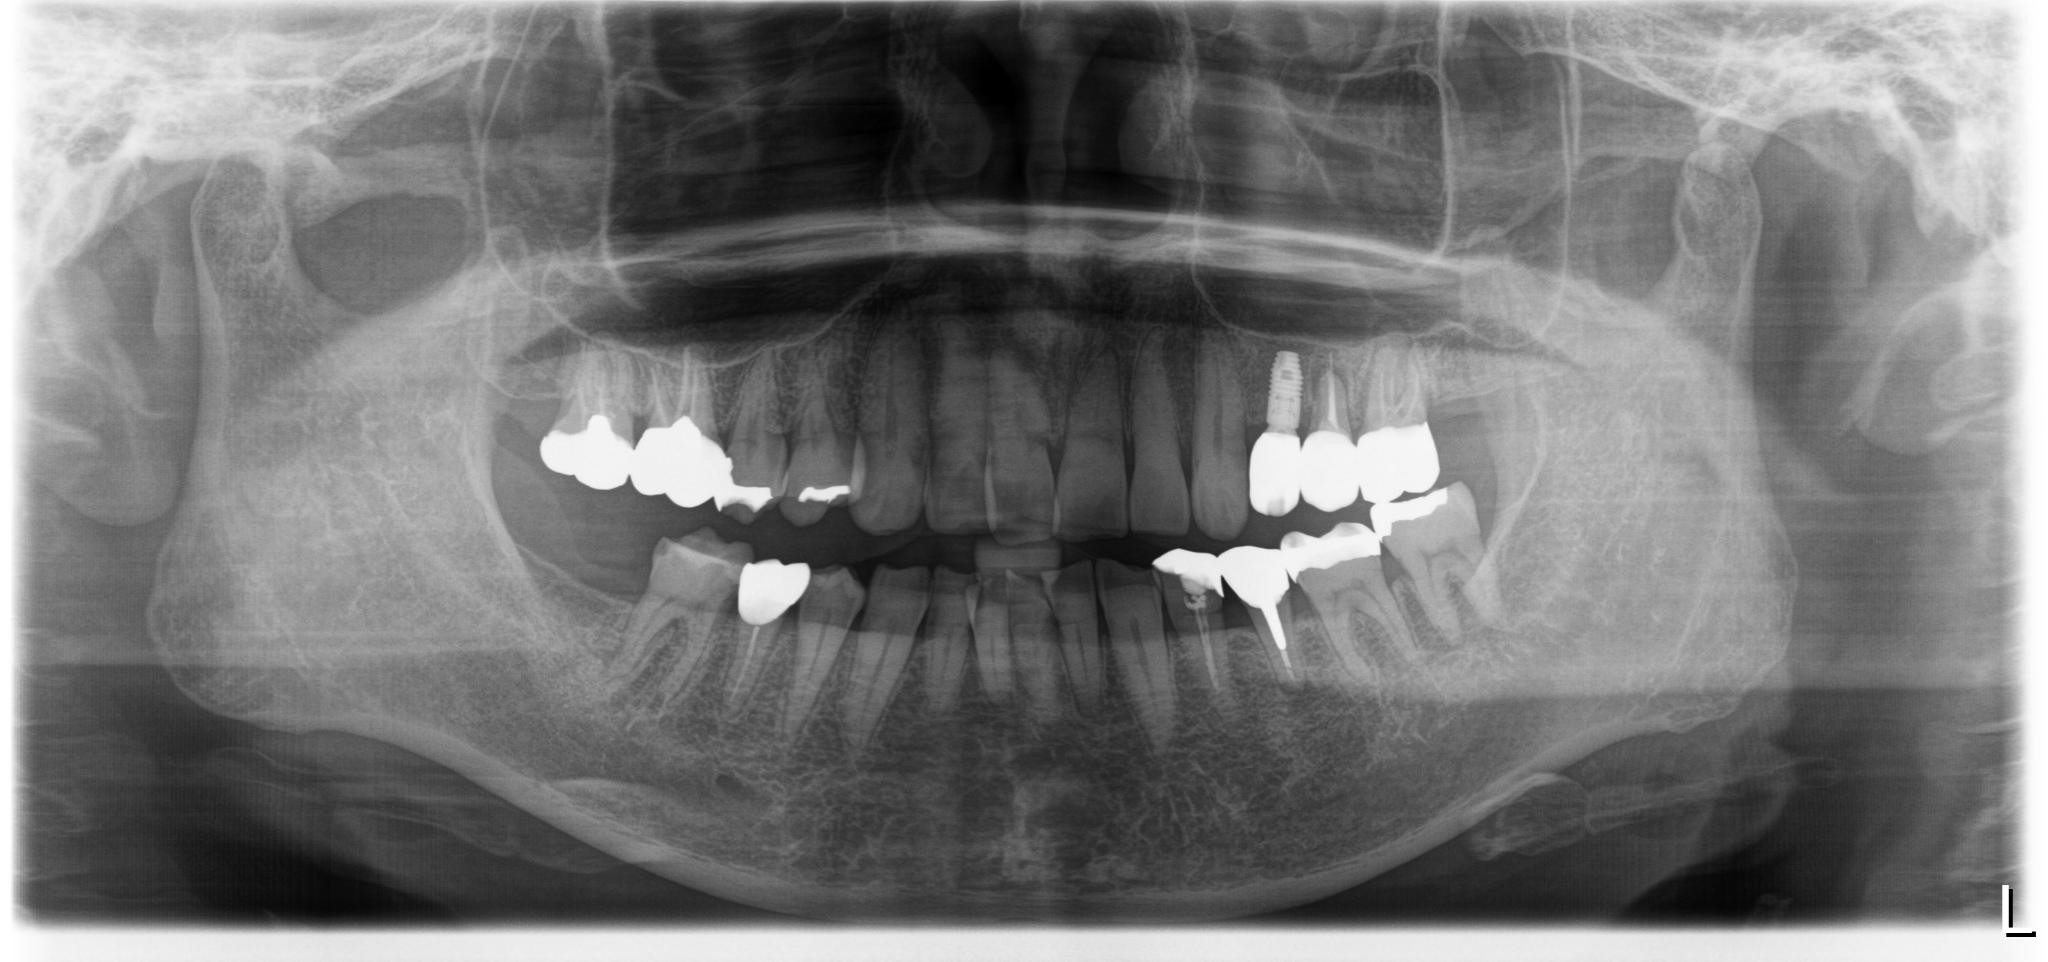

治療後レントゲン画像